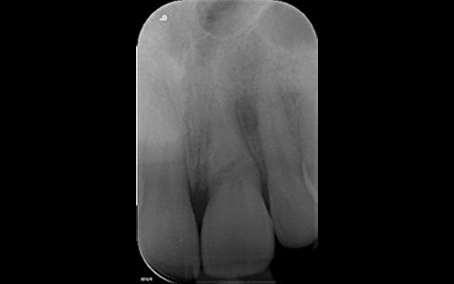

Dr Rupal Patel – Specialist Periodontist

Radiograph 1 2018

Radiograph 1 2023

Radiograph 2 2018

Radiograph 2 2023